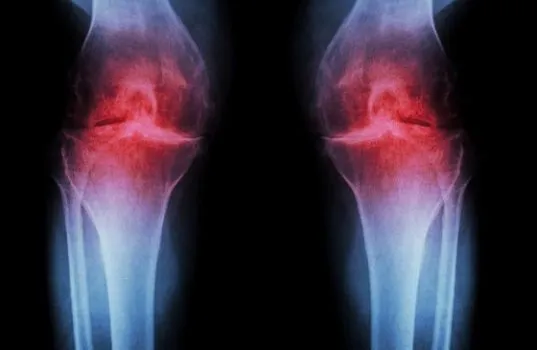

Η οστεοαρθρίτιδα είναι μια μορφή εκφυλιστικού πόνου στις αρθρώσεις που προκαλείται από τη φθορά τους. Oσο ο άνθρωπος μεγαλώνει, ο χόνδρος που προστατεύει τις επιφάνειες των οστών, χάνει την ελαστικότητά του και αρχίζει να φθείρεται.

Αυτό έχει ως αποτέλεσμα τα οστά να τρίβονται μεταξύ τους και αυτή η τριβή οδηγεί σε φλεγμονή των αρθρώσεων.

Η ΟΑ συνήθως επηρεάζει τις αρθρώσεις των χεριών και των ποδιών, συμπεριλαμβανομένων των δακτύλων, των καρπών, των γονάτων, των αστραγάλων και των γοφών. Το κάτω μέρος της πλάτης είναι επίσης μια συνηθισμένη πηγή πόνου της οστεοαρθρίτιδας.